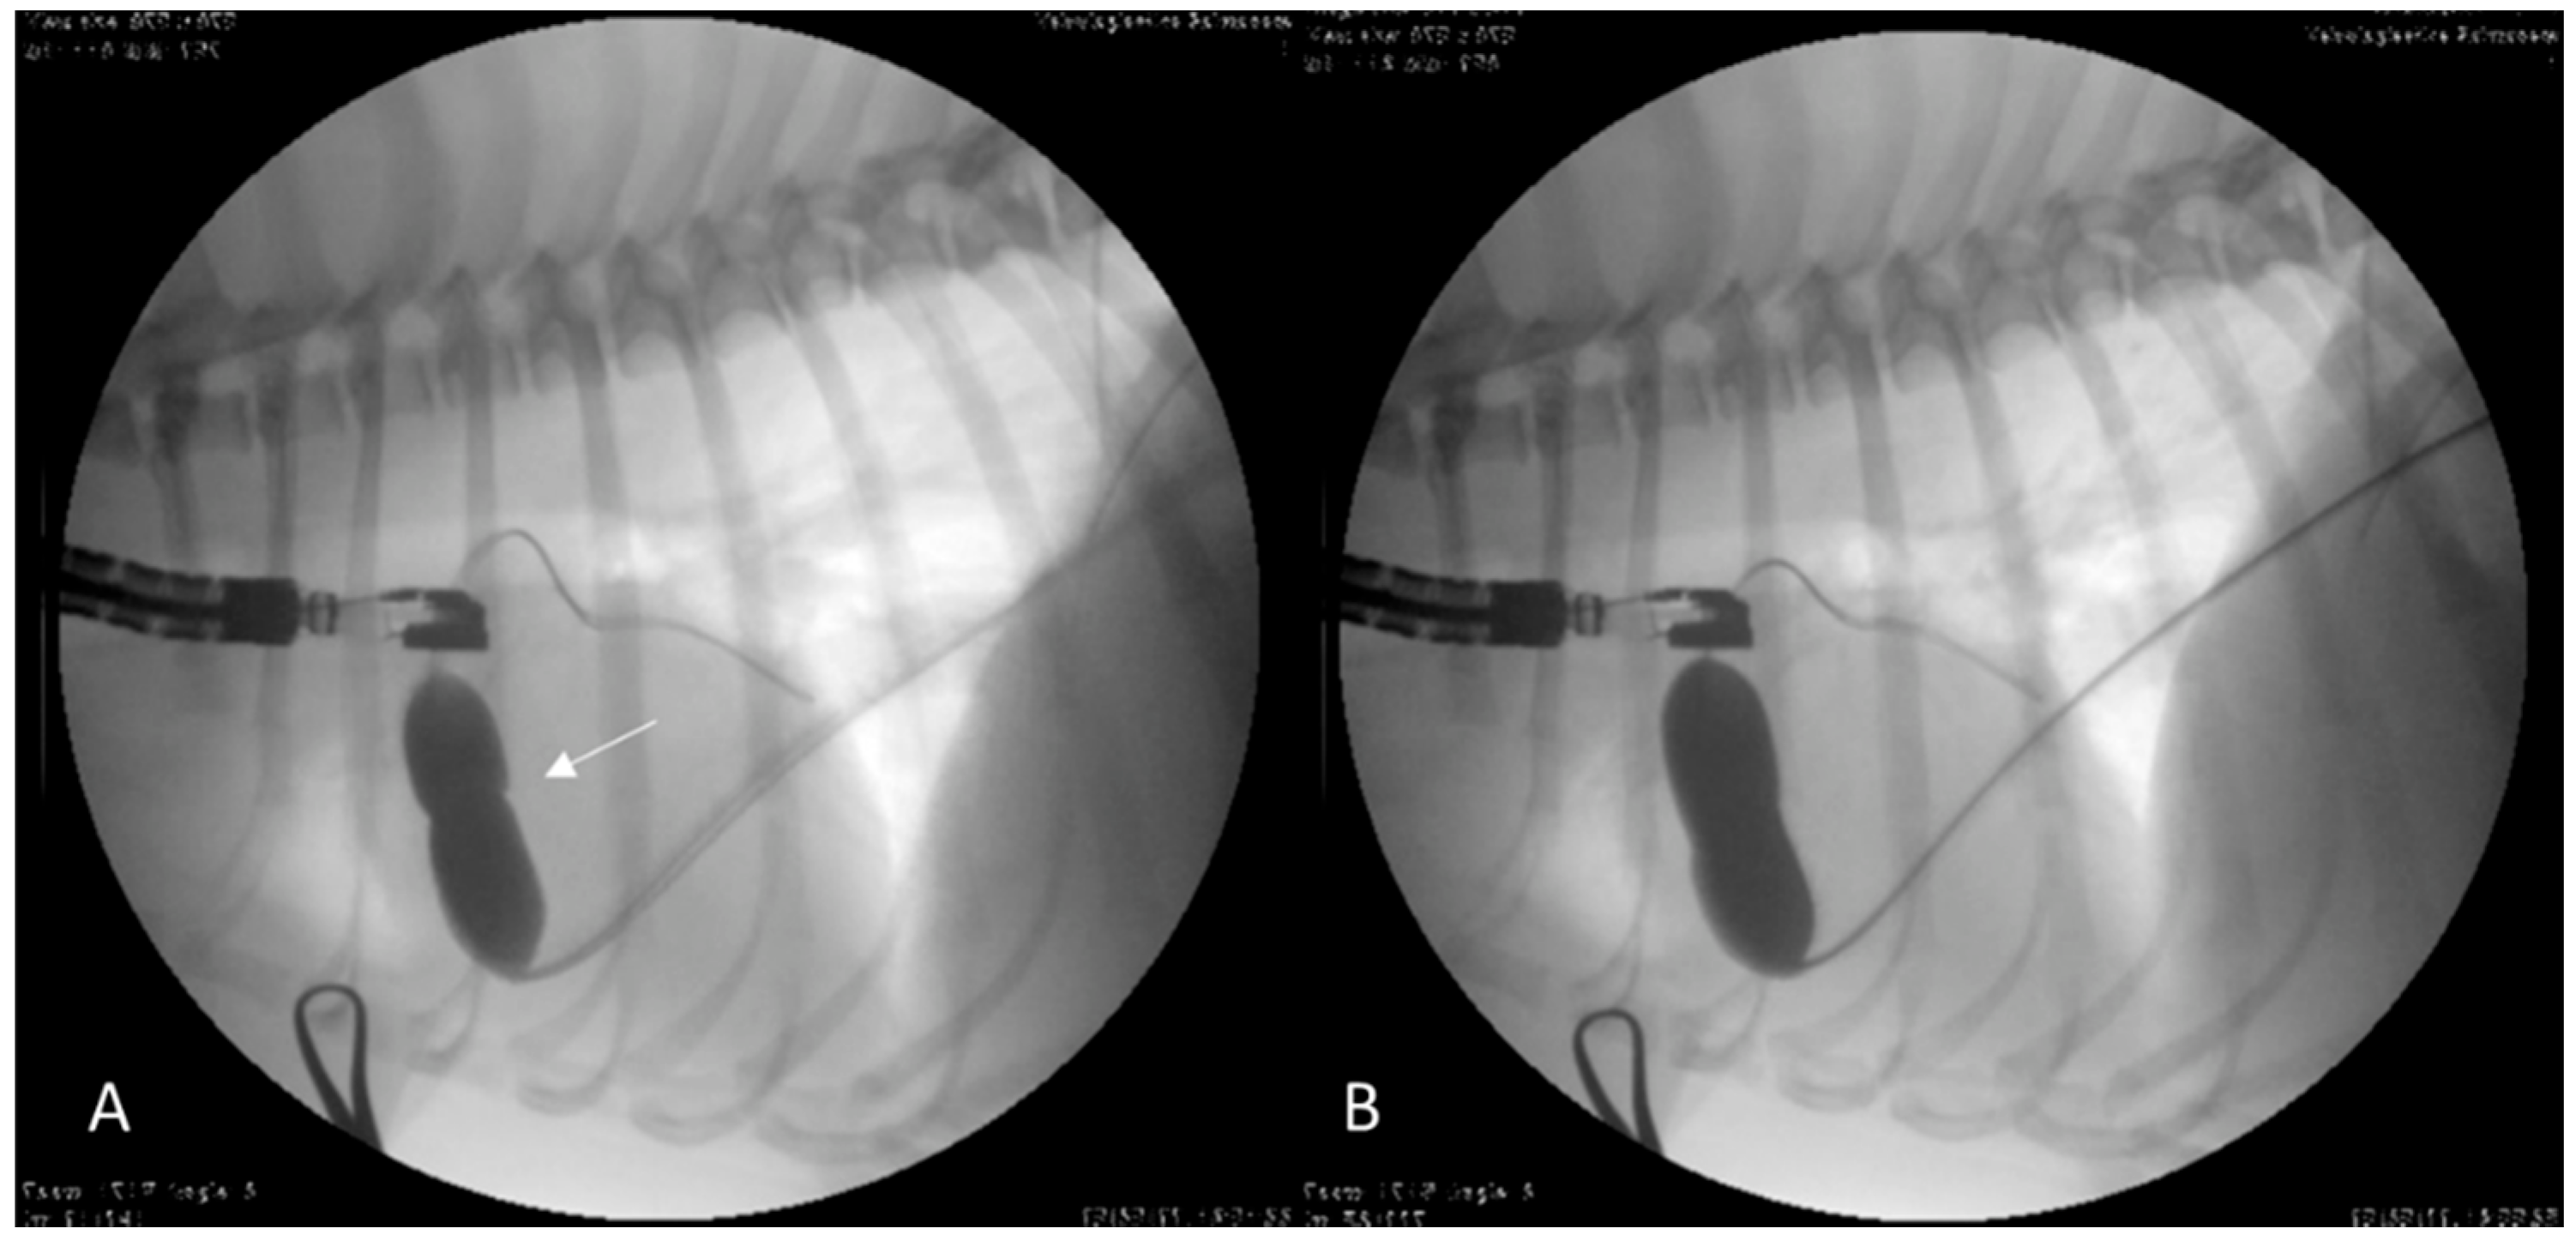

2.2. Case 2

2.3. Case 3